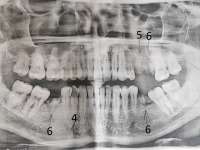

>>1326884 (OP)

сап медач, удалили зуб мудрости (точь-в-точь было как на пике, только он еще торчал малость). Прошла неделя. Ноет пара соседних зубов. Еще один зуб стал гиперчувствителен к холоду (при промывании ноет пока отвар не нагреется щекой).

Хирург говорит подождать, скорее всего нерв задели при удалении так как удаление сложно. Это возможно?

Говорит если в течении трех недель не пройдет будут с терапевтом смотреть че у меня. До этого на зубы эти не жаловался.

Может стоит самому сходить и сделать КТ челюсти чтобы узнать что у меня там?